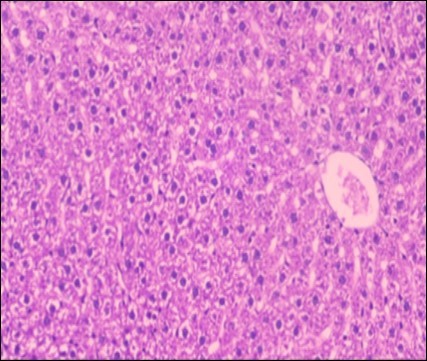

Effect of Ator, Fennel and Their Combination on the Liver of Obese Rats

The histological examination of the livers of control rats feeding standard diet showed normal architecture hepatocytes, blood sinusoid and central vein, figure 6. The rats which were fed on a (HFD), showed swollen hepatocytes with vacuolated cytoplasm filled with fatty infiltration, congested central vein and disappearance of blood sinusoids, figure 7. By comparison, the liver of rats that were treated by fennel after obesity and control mice observed nearly normal of the hepatocytes with eosinophilic cytoplasm, central vein and clear blood sinusoids and more bi-nucleated cells, figure 8. While examination of rats' liver that were treated by Ator and after the obesity appears, they showed mild fatty change in hepatocytes, few hepatocytes retain is eosinophilic cytoplasm and central vein figure 9. Liver of rats that were treated by fennel and Ator after obesity and control rats are showing nearly normal hepatocytes figure 10.

Figure 10.Photomicrograph of liver section of treated rat both with both fennel herb and Ator drug showing nearly normal hepatocytes (H&E) (40X).